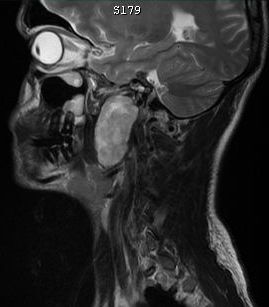

| Trigeminus - Neurom | 78-jährige Frau mit Trigeminusneuralgie seit 10 Jahren. Seit 8 Jahren gering größenprogredienter Tumor im rechten Kleinhirn-Brückenwinkel. | ||

![]() |

![]() ![]() | ||